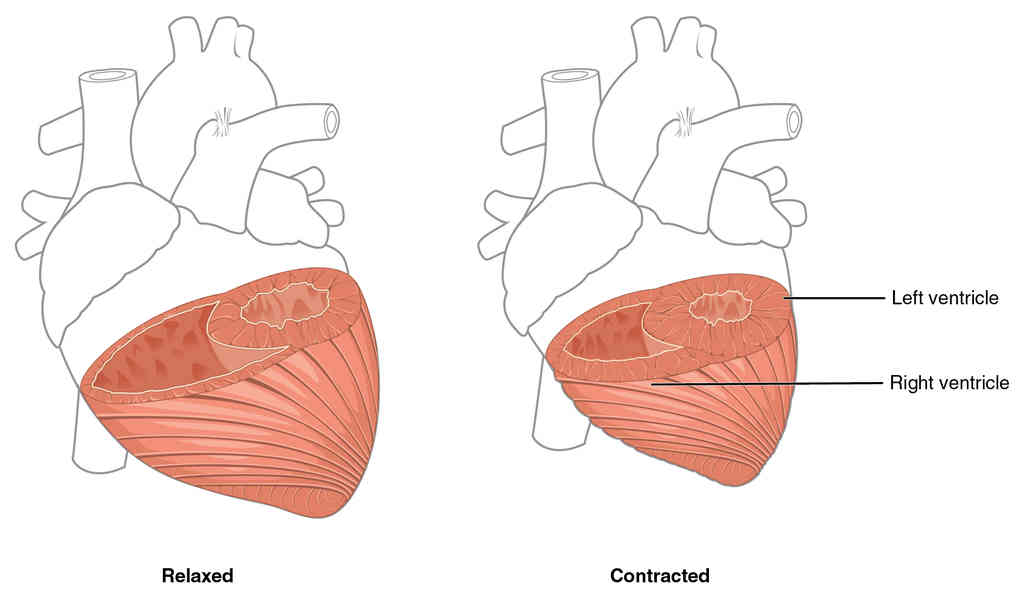

This page is under construction. For now, it is just a resource of the images found in the OpenStax Anatomy and Physiology Handbook. It wil slowly change into a revision tool. Each slide has a number. Use this to refer to the slide. When completed, it will have an unlabelled section, with labelled slides in parallel. On the unlabelled slides, write your answer and use the labelled slide to assess yourself. Keep track by also noting the number on each slide. Improvement at each attempt is important, more so than full marks on a first attempt.